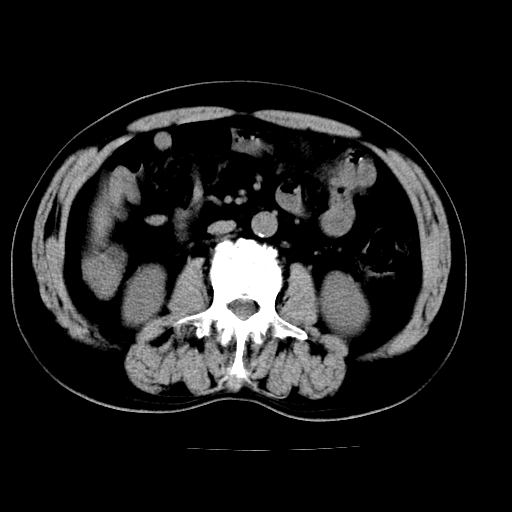

肝左叶占位性病变,并胆管扩张,符合胆管细胞癌ct表现,门脉左支受累,左肾囊肿。窗宽太窄了,其他的看不清

左叶胆管细胞癌累及胆总管,门脉左支受侵,慢性胆囊炎胆结石,左肾小囊肿

肝左叶不规则软组织肿块影,边缘不规整邻近肝实质受累分界不清;肝内胆管(左叶)明显扩张成“软藤状”,诊断:肝左叶胆管细胞癌。胆囊钙乳症。

支持 1肝左叶肝内胆管细胞癌伴胆总管及门脉左支受侵。2胆囊钙乳症。

支持 1)肝左叶胆管细胞癌伴胆总管及门脉左支受侵。2)胆囊钙乳症。